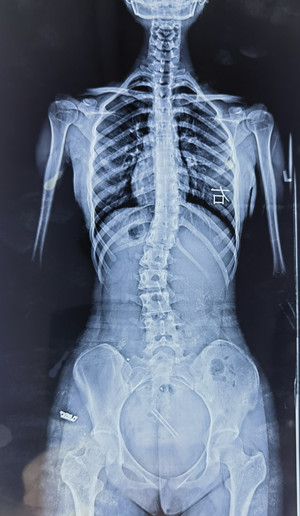

脊柱側(cè)彎拍X片

我的孩子可能脊柱側(cè)彎了,想拍一個(gè) “ 站立式全脊柱正側(cè)位X片 ” 。

您也可以給醫(yī)生看上圖,問下醫(yī)生能不能拍這樣的X片(并不是所有醫(yī)院都有能力拍這樣的X片)。